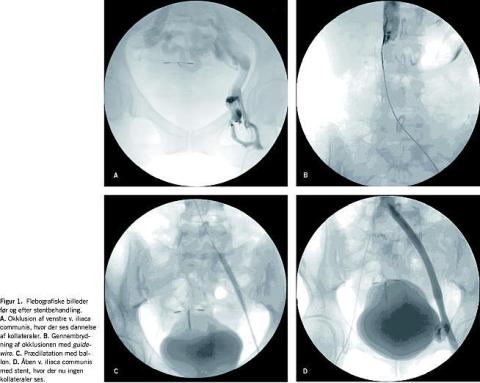

Den endovaskulære behandling bestod i, at man i lokalanæstesi ved ultralydvejledt ipsilateral perkutan adgang gennem v. femoralis communis foretog flebografi. Ved hjælp af denne kontrastundersøgelse kunne en guidewire manipuleres igennem okklusionen, som blev prædilateret med en ballon. Herefter kunne der anlægges selvekspanderende stent (Wall-stent, Boston Scientific, eller Smart-stent, Cordis) i den pågældende okklusion (Figur 1 ). Alle patienter fik under proceduren injiceret 5.000 IE heparin intravenøst. Patienterne blev mobiliseret fire timer efter stentanlæggelsen. AK-behandling med tinzaparin 100 IE pr. kg to gange dagligt og vitamin K-antagonist-behandling (warfarin) blev påbegyndt postoperativt. Tinzaparin blev administreret, indtil international normalized ratio (INR) lå i terapeutisk niveau (INR 2-3), og AK-behandlingen blev fortsat i minimum seks måneder. Patienter med svær trombofili fik vedvarende warfarinbehandling. Det øvrige postoperative regimen bestod i anvendelse af graduerede korte kompressionsstrømper kl. II.

Postoperativ kontrol af patienterne skete efter seks uger, seks måneder, 12 måneder og efterfølgende hvert år. Ved hver kontrol blev patienterne vurderet klinisk, og der blev foretaget UL-undersøgelse af den behandlede ekstremitet (Figur 2 ). Her blev det vurderet, om venesegmentet med den anlagte stent var åbent, og patienternes veneklapfunktion blev undersøgt for at konstatere, om der var refluks i den pågældende ekstremitet.